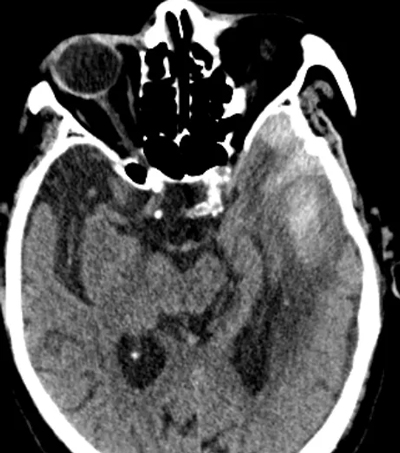

頭部CT顯示

左側(cè)顳部硬膜下血腫、蛛網(wǎng)膜下腔出血

達(dá)到手術(shù)指證